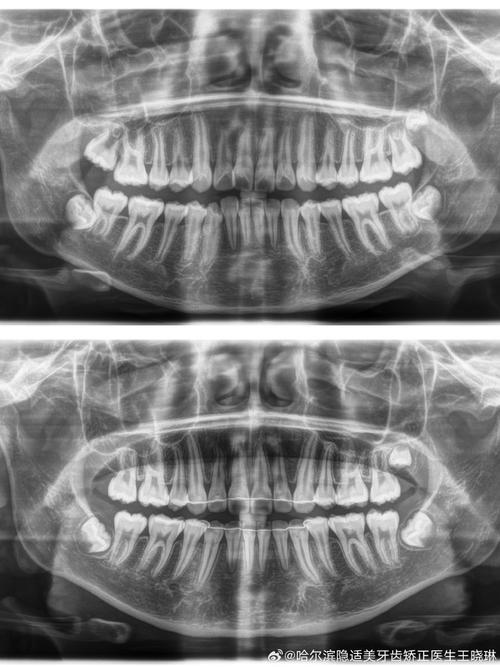

正畸侧位片的拍摄需严格遵循标准化流程:患者采用自然头位,眶耳平面(由眶下缘最低点与外耳道上缘连线构成)与地面平行,X线中心线对准外耳道上方5cm处,胶片或探测器距离中矢面15cm,曝光参数根据患者年龄及体型调整(成人通常为60-70kVp,8-15mA),确保图像清晰显示颅骨轮廓、颌骨形态、牙齿牙根及周围骨结构,避免因头部倾斜、咬合干扰或伪影导致标志点模糊。

正畸侧位片的测量依赖于对关键解剖标志点的识别,临床中通常将标志点分为骨骼与牙齿两大类,共14个核心点(简称“77分析体系”),其定义及临床意义如下表所示:

基于“77分析体系”的标志点,可计算多项关键测量指标,用于评估骨骼型、牙齿位置及软组织侧貌:

骨骼测量指标

- SNA角:由蝶鞍点(S)、鼻根点(N)、上齿槽座点(A)构成,正常值82°±4°,反映上颌骨相对于颅部的位置,SNA角增大提示上颌前突,减小提示上颌后缩。

- SNB角:由蝶鞍点(S)、鼻根点(N)、下齿槽座点(B)构成,正常值80°±4°,反映下颌骨相对于颅部的位置,SNB角增大提示下颌前突,减小提示下颌后缩。

- ANB角:由上齿槽座点(A)、鼻根点(N)、下齿槽座点(B)构成,正常值2°±2°,是判断上下颌骨矢状关系的关键指标,ANB角>4°提示Ⅱ类骨性错颌(上颌前突或下颌后缩),<0°提示Ⅲ类骨性错颌(下颌前突或上颌后缩)。

- SN-Me角:由蝶鞍点(S)、鼻根点(N)、颏下点(Me)构成,正常值68°±5°,反映下颌平面(通过Me点与下颌角点的连线)相对于颅底平面的倾斜度,角度增大提示下颌平面陡峭,面部垂直高度增加;减小提示下颌平面平缓,面部垂直高度不足。

牙齿测量指标

- UI-SN角:上中切牙长轴与SN平面的夹角,正常值105°±6°,反映上中切牙的倾斜度,角度增大提示上切牙唇倾,减小提示舌倾(需注意牙根位置,避免舌倾过度导致牙根吸收)。

- LI-MP角:下中切牙长轴与下颌平面(MP)的夹角,正常值95°±6°,反映下中切牙的倾斜度,临床中常要求下切牙控制在90°-110°,避免过度唇倾导致牙龈退缩或舌倾影响咬合功能。

- U1-NA距:上中切牙切缘至NA连线的垂直距离,正常值4mm±2mm,反映上切牙相对于上颌骨的突度,距离过大提示上切牙前突,需内收;过小提示舌倾,可能需唇展。

- L1-NB距:下中切牙切缘至NB连线的垂直距离,正常值4mm±2mm,反映下切牙相对于下颌骨的突度,临床意义与U1-NA距类似,是下颌切牙矫治的重要参考。